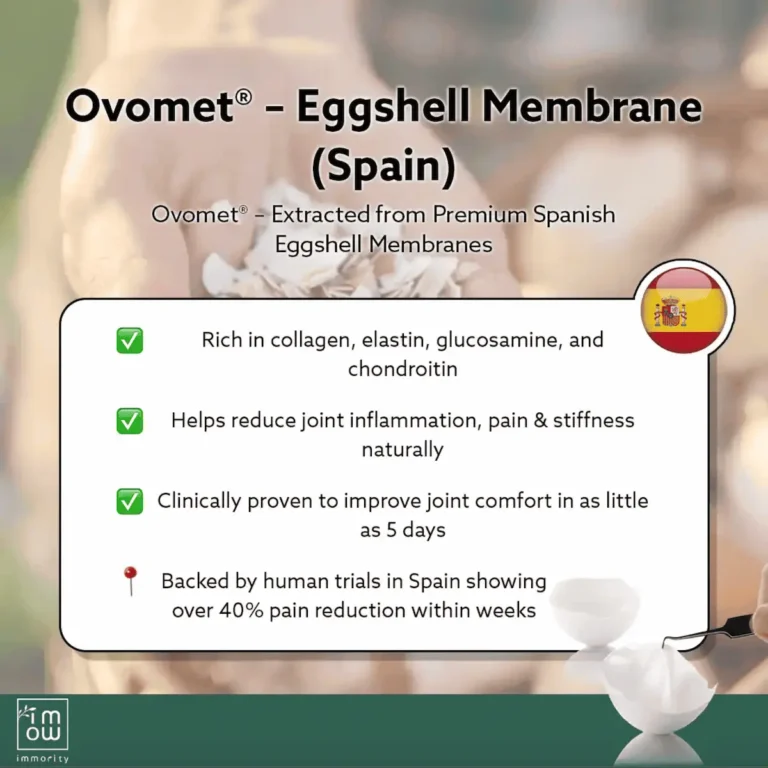

A premium natural extract from eggshell membrane developed in Spain. Contains over 500 active compounds, including collagen, hyaluronic acid, glucosamine, and chondroitin.

- Reduces joint inflammation naturally

- Rebuild, replanish damaged cartilage & Fluid

- Relieves knee pain in 7 days